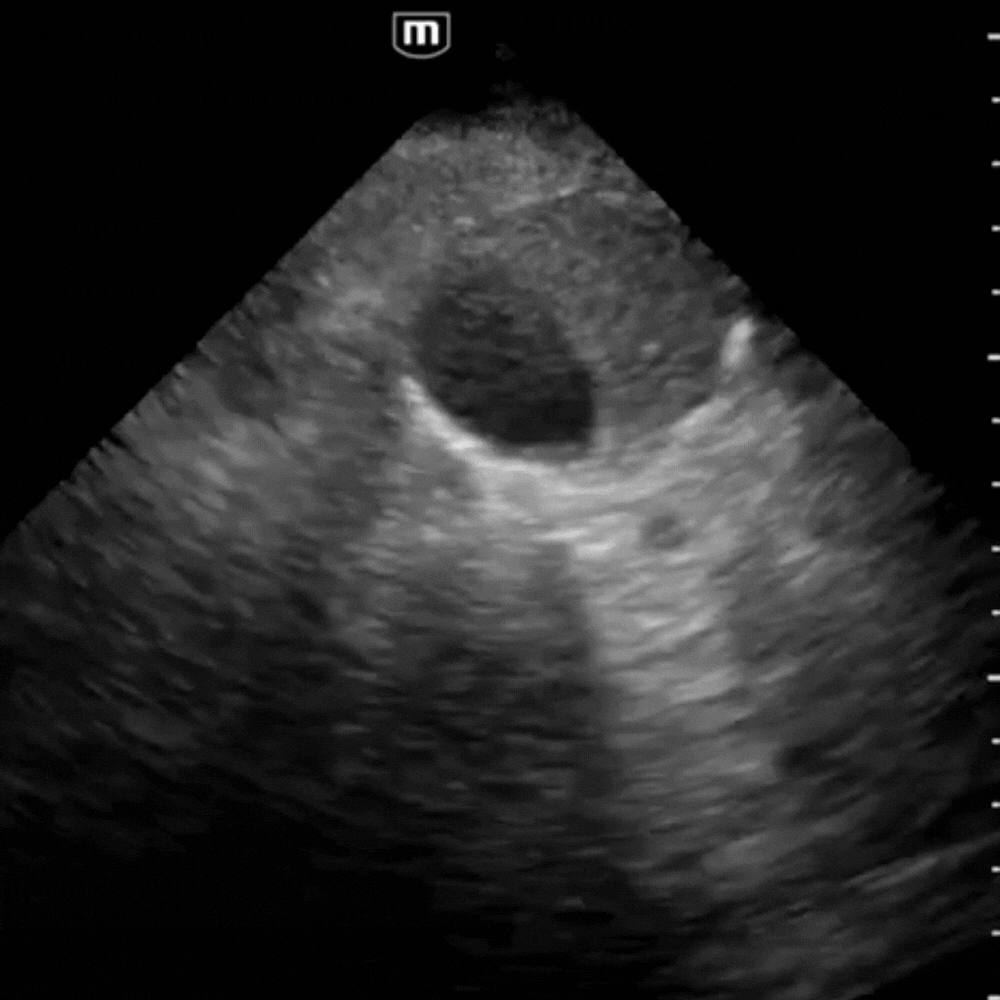

⚠️ Signes de Pathologie

- Anévrysme fusiforme ou sacculaire : dilatation > 3 cm, souvent avec calcifications pariétales.

- Thrombus mural : zone échogène pariétale sans flux au Doppler.

- Rupture : hématome rétro-péritonéal hétérogène, parfois difficile à distinguer ; rechercher un épanchement libre.